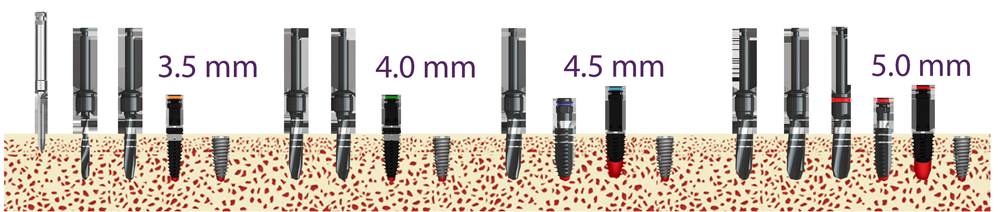

Схема на някои размери имплантати от системата Superline на Dentium - Южна Корея. Двата размера вляво дават нагледна представа за разликата между класическия конусовиден имплант и имплантата с широка шийка, удачен за имедиатно имплантиране. Първият имплант е с диаметър 4.8 мм. на тялото и 5 милиметра на шийката; вторият е също с 4.8 на тялото, но с 6 милиметра диаметър на шийката. Вижда се разликата в заострянето - различният тейпър, както интелигентно обичат да се изразяват ендодонтите. Крайният зъбен имплант вдясно е с тейпър като на средния, но с по-голяма дебелина на тялото и шийката - съответно 5.8 и 7.0 мм. Имплантатите с широка шийка намират особено голямо приложение в областта на моларите.

Хирургичен протокол за поставяне на имплантати от

серия IS2. След пробиване на костта

с калиброващата фреза горната 1/3 до 2/3 се калиброват допълнително с

костния метчик - tap drill. След това се поставя

зъбният имплант, който е със заострена форма -

tapered

design. Формата на импланта е конструирана така че при

достигане на дълбочината на разпробиване да се достигне оптималният въртящ

момент - за имедиатно натоварване той е 35 - 40 N/cm,

както стана въпрос по-горе. Важно е подходящият торк да се достигне при

първото завинтване на импланта в костта - ако тогава се постигне по-голям

въртящ момент, е необходимо да се върне назад имплантът на 1/2 до 1 оборот,

при което самият той действа като калиброваща фреза. При необходимост това

може да се повтори дори до 3 или 4 пъти. Всяко развиване и завиване обаче

създава допълнителна костна травма поради компресията, а и донякъде нарушава

кръвоснабдяването на костта - поради това е най-добре още при първото

завинтване имплантът да достигне оптималния торк. За това обаче се изисква

известен клиничен опит от страна на имплантолога, тъй като определянето на

костната плътност е основно по субективни критерии. При съчетание на голям

имплантатен размер с първоначално достигнат торк от 35

N/cm зъбните импланти могат да бъдат натоварвани

успешно дори и в критичния период от 6 - 8 седмица постоперативно.